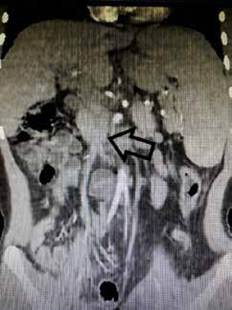

Al ingreso presentaba signos vitales normales, con palidez mucocutánea y esplenomegalia moderada no dolorosa; tenía hemoglobina de 7 gramos por decilitro (g/dL) y plaquetas de 65.500 por microlitro (mcL). Se realizó tomografía abdominal contrastada con fase portal, encontrando degeneración cavernomatosa de la porta (figura 1), y el doppler espleno-portal mostró vena porta de 8 mm de diámetro con evidencia de formaciones venosas colaterales a nivel del hilio hepático y esplenomegalia. Adicionalmente se realizó arteriografía de vasos abdominales y portografía retrograda que evidenciaron permeabilidad de la arteria hepática, vena porta intrahepática y vena mesentérica superior. Se realizó biopsia hepática percutánea guiada por tomografía computarizada (TC), donde se observó normalidad del parénquima hepático. Debido a los hallazgos previos y al sangrado repetitivo, se indicó la realización de una derivación meso-Rex.